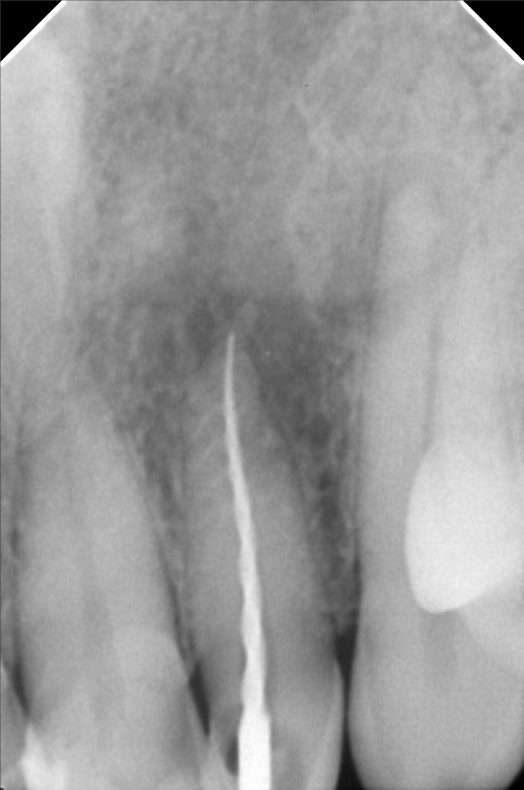

- 10/05/21 -0p/ Lc 11m/21M *22 subject for rct *11 distal repeat lc/ 21 repeat lc/ 12 lingual repeat lc 10/15/21- rct 22mm/ apical abcess laser done apexcal 10/22/21 - LC #12 mesial #11 Lc Distal #21 Distal LC #22 veneer #22 obturate- 22mm guttaflow 04/02/22- veneer due to spaces #41/42/43/31/32/ shade A3/ esthetica 08/25/2023- Cleaning veneer re-polish 11/12/22/21

- bonifacio2.jpg